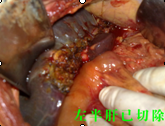

“病情嚴(yán)重,盡快手術(shù)?!薄T主任如是說(shuō)?;颊呷朐汉?,譚主任立即召集醫(yī)務(wù)人員進(jìn)行術(shù)前討論,安排醫(yī)生完善各種術(shù)前檢查,制定周密的手術(shù)方案。第二天,他即帶領(lǐng)腫瘤外科經(jīng)驗(yàn)豐富的醫(yī)生為患者實(shí)施了肝門(mén)部膽管癌切除+膽囊切除+左半肝切除,右肝管空腸R-Y吻合術(shù)。在手術(shù)中,由于患者膽囊梗阻部位非常高,腫塊生長(zhǎng)長(zhǎng)度已達(dá)到左右肝總管交界處,手術(shù)過(guò)程中極容易損傷門(mén)靜脈、肝動(dòng)脈及腔靜脈。先切除膽囊,后分離肝、十二指腸韌帶,骨骼化門(mén)靜脈、膽總管、肝動(dòng)脈。見(jiàn)腫塊位于高位膽總管,予以切除左肝總管及肝左葉,行R-Y吻合,整個(gè)手術(shù)僅用了6個(gè)小時(shí),術(shù)中出血極少,手術(shù)過(guò)程非常順利,術(shù)后及時(shí)給予抑酸、抗炎、護(hù)肝補(bǔ)液等對(duì)癥支持治療。經(jīng)過(guò)精心地治療和周到地護(hù)理,現(xiàn)患者恢復(fù)良好。據(jù)統(tǒng)計(jì),此手術(shù)切除機(jī)率不到5%。